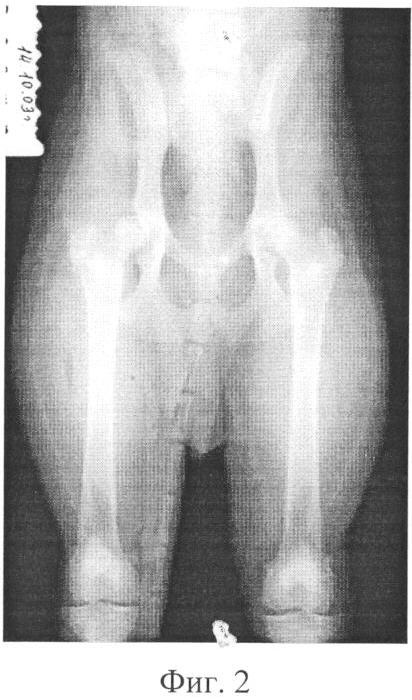

Фиг.2 – рентгенограмма тазобедренного сустава собаки в день оперативного вмешательства;

В ходе операции осуществили доступ к правому тазобедренному суставу, произвели вскрытие полости сустава, выполнили резекцию дорсального края вертлужной впадины с выделением и удалением ее краевого фрагмента величиной 1,3×0,5 см. После этого произвели тенотомию связки головки бедренной кости; бедро ротировали кнаружи на 20° и сдвинули в направлении сформированного дефекта вертлужной впадины. Затем провели тщательный гемостаз и ревизию операционной раны, после чего ее послойно и наглухо ушили (фиг.2).